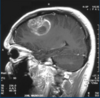

give features of grade IV glioma

- most common - most aggressive - glioblastoma multiforme (GBM) - spread by tracking through white mater and CSF pathway

adequate cerebral imaging: - CT - MRI - PET - (angiography) if suspecting metastasis: - CT chest/abdo/pelvis - mammography - biopsy skin lesions/lymph nodes

59

glioblastoma multiforme magaement options

- complete surgical excision impossible > biopsy or debulk only - steroids - anticonvulsants - radiotherapy - chemotherapy > temazolamide